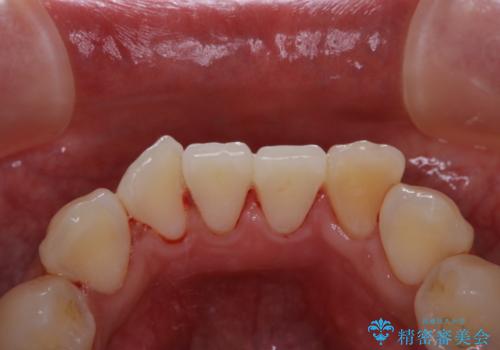

インビザラインでの矯正治療前にPMTCで歯のクリーニング

- 矯正治療の前にクリーニング希望で来院されました。PMTC30分コースを行いました。

PMTCは、国家資格取得者の歯科衛生士により、専門的な機械や材料を使用してのクリーニングです。一人一人の患者様のお口の状態に合わせたクリーニングを行います。

矯正治療は、歯を動かすため歯肉にも負担がかかります。そのため、矯正前にしっかりクリーニングを行い健康なお口の状態にしておくことが大切です。